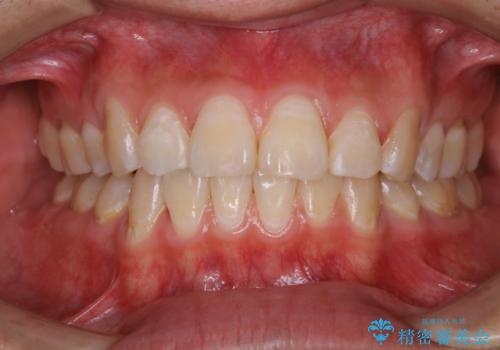

- 定期健診で全体的のチェックとクリーニング希望で来院されました。PMTC30分コースでクリーニングを行いました。

PMTCとは「Professional Mechanical Tooth Cleaning」の略で、専用の機器を使った歯のクリーニングです。

審美的面だけではなく、歯周病や虫歯・口臭などのリスクを予防することができます。

汚れを除去することにより、症状の早期発見につながります。